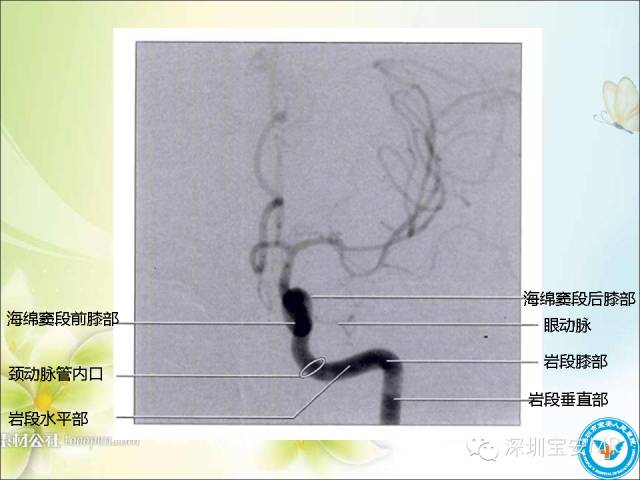

看了这么多,先来一段血管TOF的原始图像视频,对于了解颅内动脉走形及3D很有帮助的!